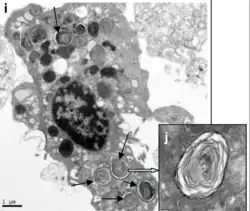

Um pneumócito é uma célula epitelial dos alvéolos pulmonares.[1] Há dois tipos de pneumócitos, os de tipo I, que constituem 40% das células e ocupam 90% da superfície do alvéolo e os de tipo II, que constituem 60% das células e ocupam apenas 10% da superfície do alvéolo.[2] [3]